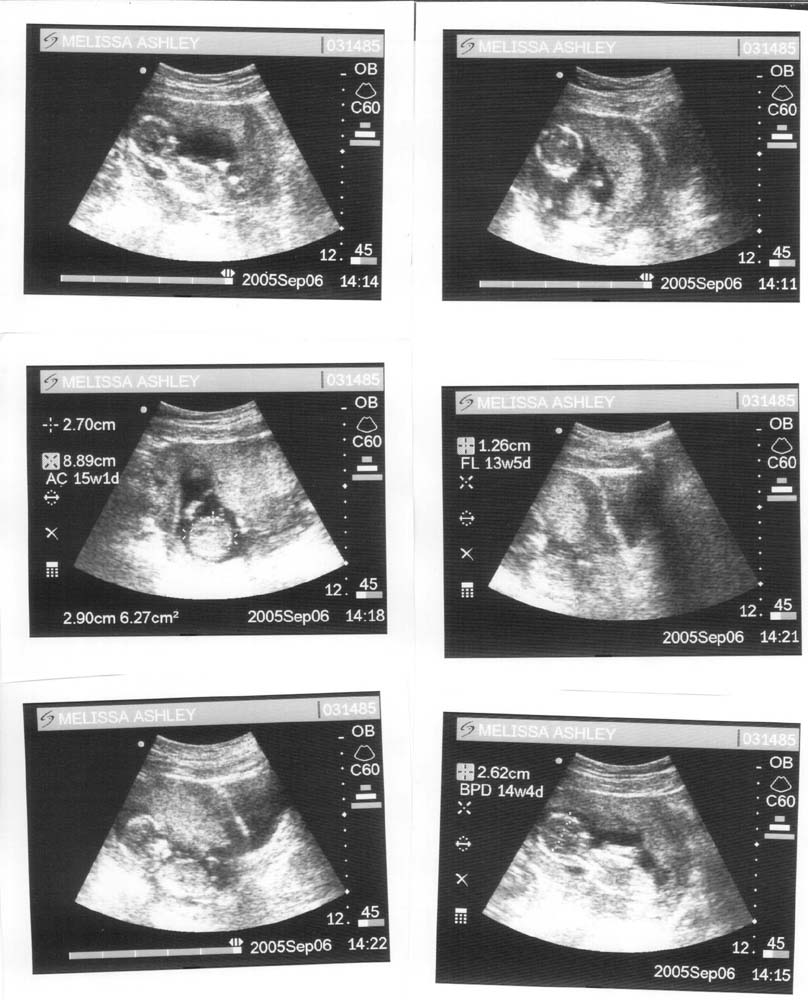

BOY OR GIRL??

September 05